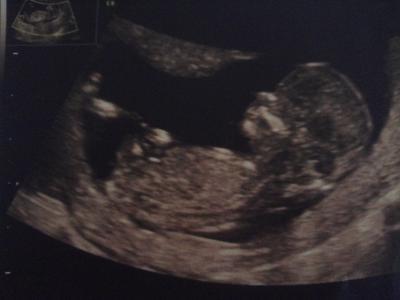

Hallo ihr Lieben, ich durfte auch heute zum Ersttrimesterscreening und kopier euch hier mal die Email an meine Familie: (sorry, bin zu faul, dass alles nochmal zu schreiben) Heute waren wir zum Ersttrimester Screening in Düsseldorf. Und es ist alles in bester Ordnung. :) Der kleine Bauchbewohner hat ordentlich rumgezappelt und sich immer wieder gegen das Ultraschallgerät gestemmt das von oben die Bauchdecke nach unten drückte. Es ist alles dran und auch die inneren Organe und Blutgefäße sind bereits voll entwickelt und funktionstüchtig. Magen und Blase sind mit Fruchtwasser gefüllt, das heißt, die Nieren arbeiten bereits und wir konnten sogar das Herz hören: 162 Schläge die Minute. Erkennbar waren auch bereits zwei Blutkreisläufte und die getrennten Herzkammern. Wow, wir waren echt beeindruckt! Nach der Messung heute ist Baby 6,2 cm groß was bedeutet, dass wir ca. 3 Tage weiter sind als ursprünglich angenommen. An dem voraussauchtlichen Termin (01.04.) wollte der Arzt aber erst mal nichts ändern, es kommt sowieso wann es will. ;) Die Nackenfalte war 1,7 mm und auch das Nasenbein war darstellbar, also total unauffällig. Morgen geht es für Baby und mich dann für eine Woche in die Sonne. Wir werden uns schön am spanischen Pool die Füße hochlegen. Ein kleines Bildchen gab es auch noch. Das Outing wollen wir der Familie erst mal vorenthalten, es ist mir noch zu unsicher. Aber es wird wahrscheinlich ein Mädchen! Glückliche Grüße!

Das war ja ein toller Termin. Faszinierendes Bild! Da sieht man ja schon richtig das Gesicht!!! Oh Gott, wie süüüüüß!!! Ich wünsch Euch einen schönen Urlaub!